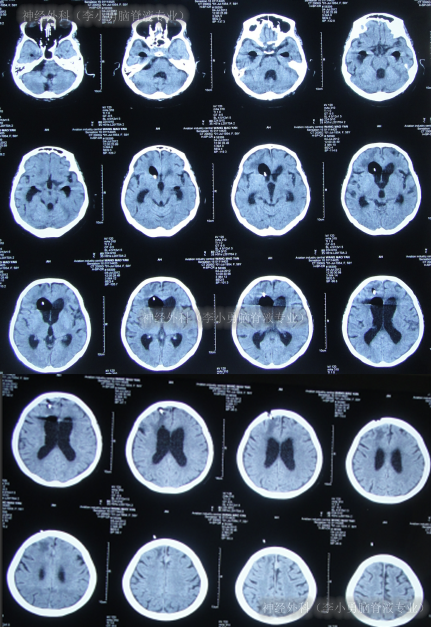

脑脊液各项化验均达标后于2012年12月4日,进行脑室腹腔分流术,术前术后头颅CT(图-19)。

图-19:术前术后头颅CT

脑室腹腔分流术后2天即2012年12月6日,查头颅CT示无异常(图-20),查肺部CT示感染进一步减轻(图-21)。

图-20:2012年12月6日头颅CT